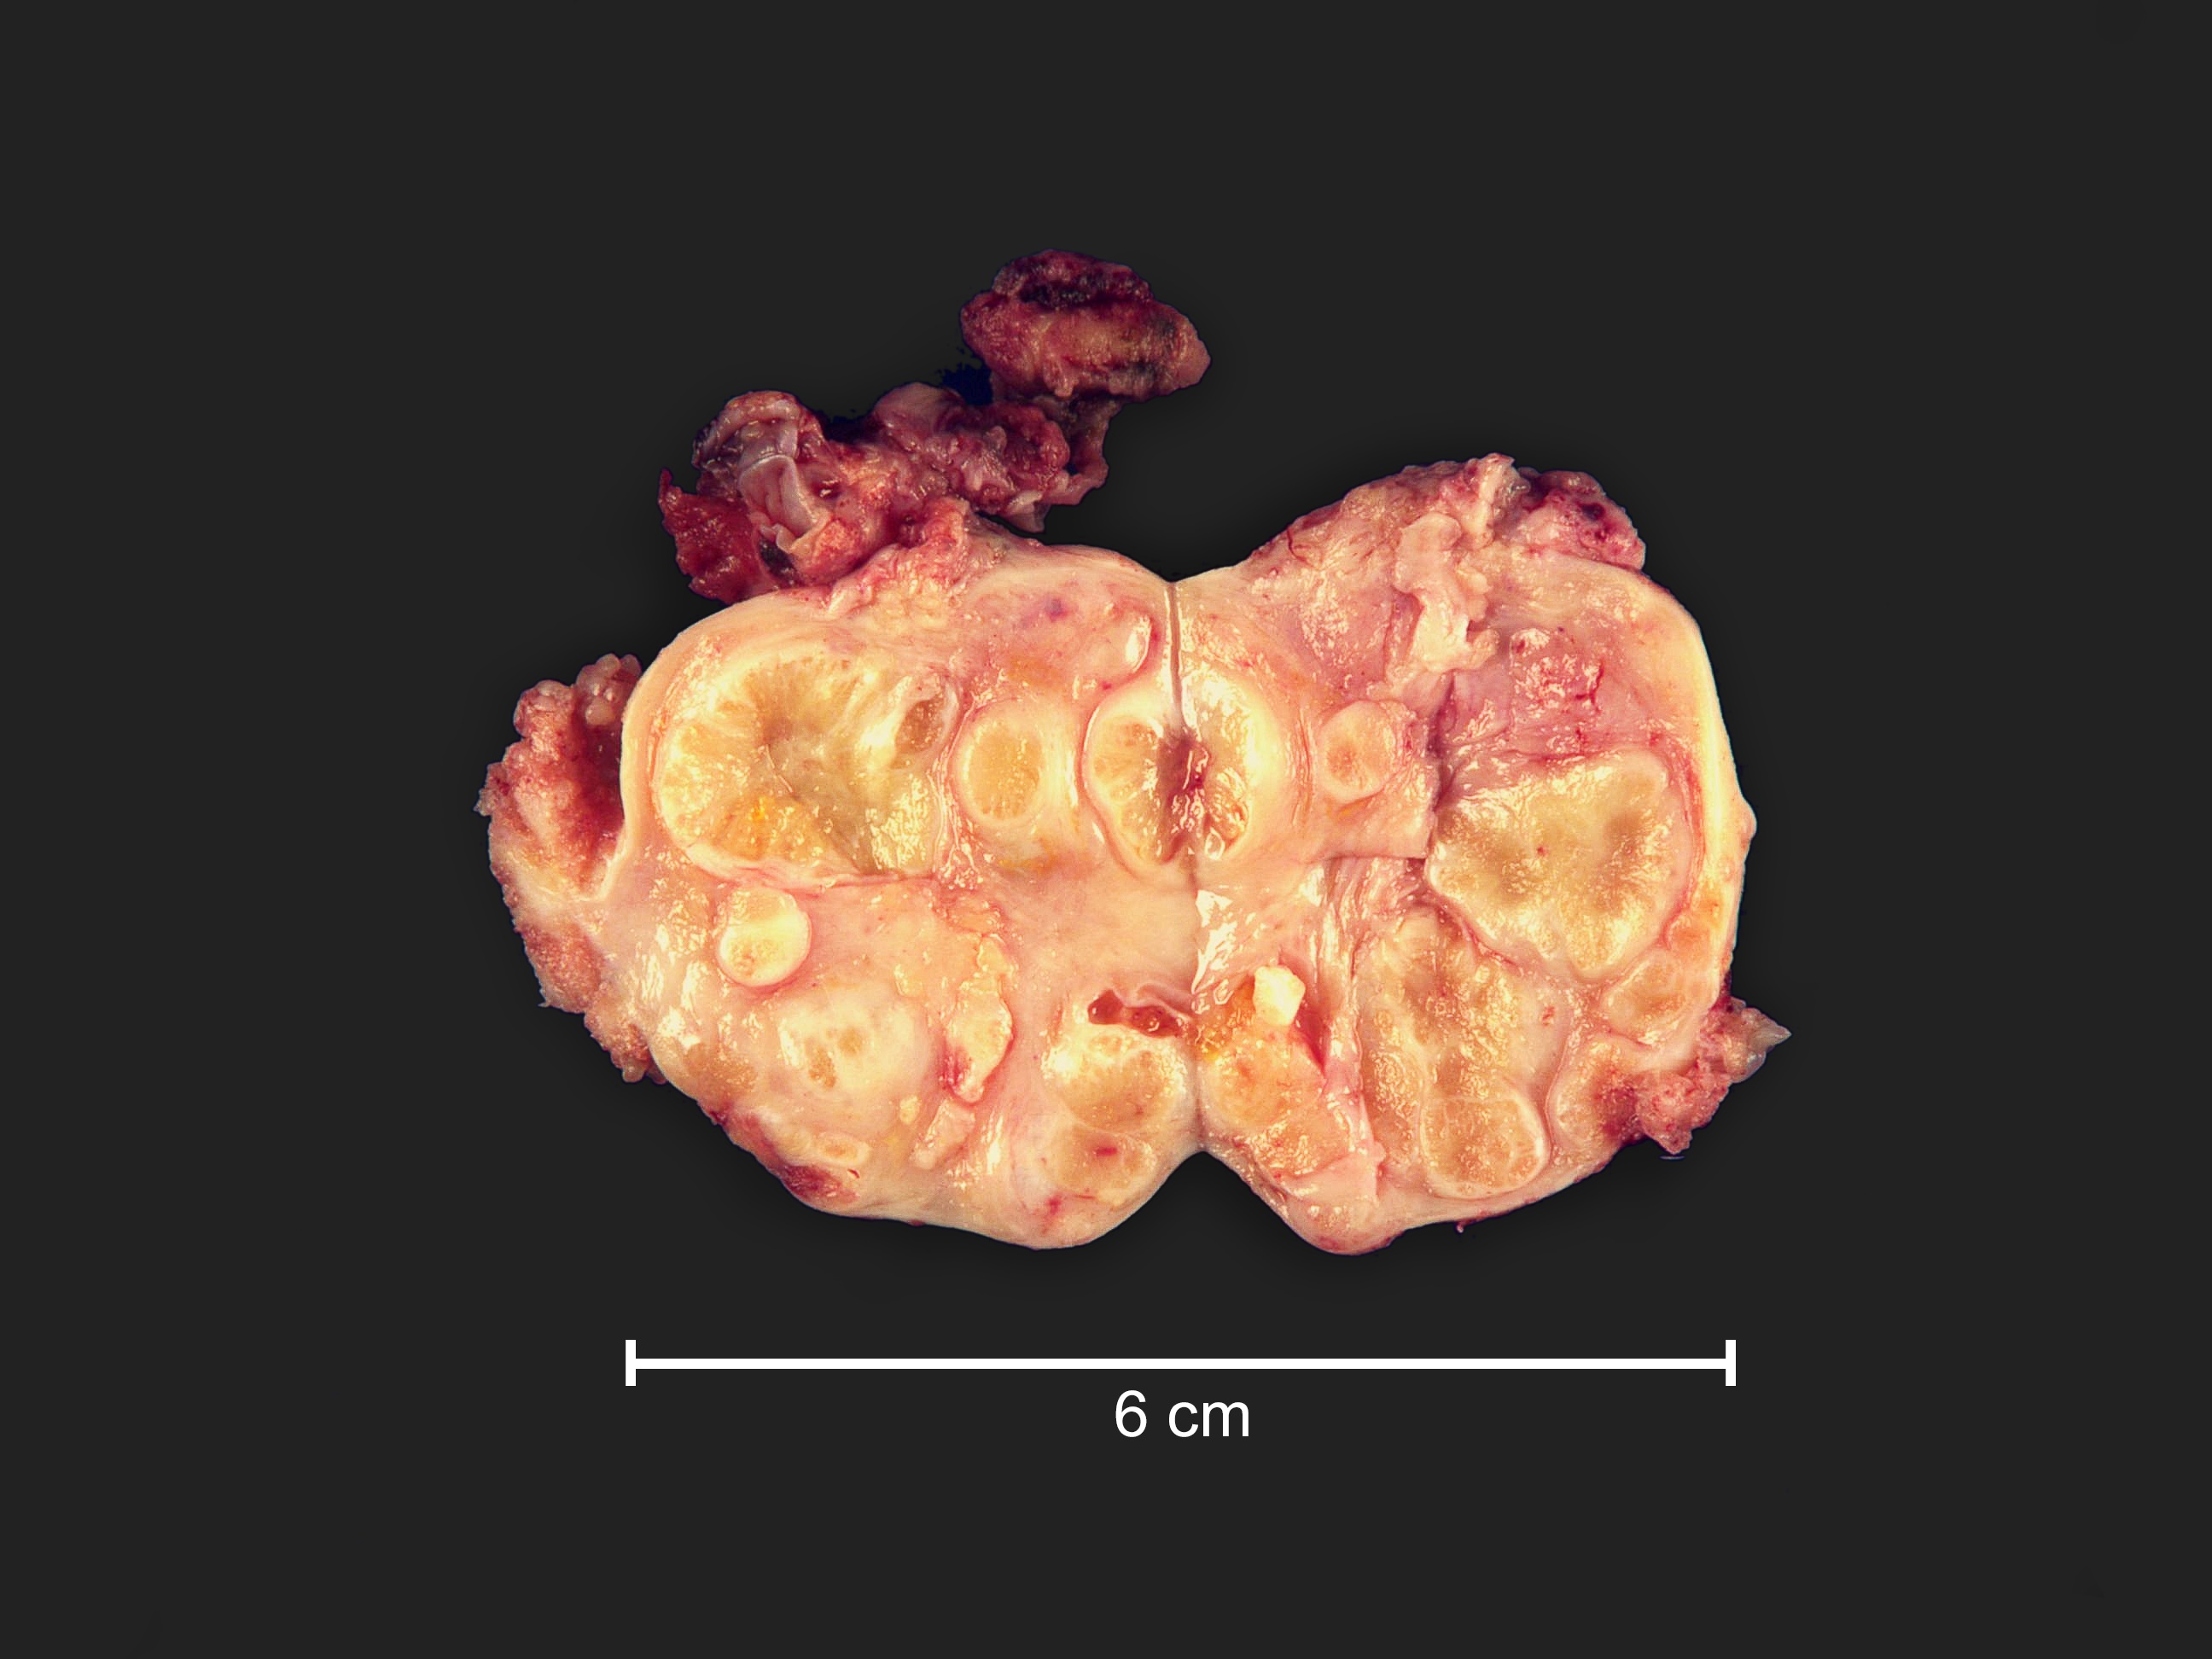

Gross description

- Often bilateral

- Fine papillary, nodular growth

- Little to no necrosis

- Calcification in the ovary and extraovarian lesions can be extensive

Gross images